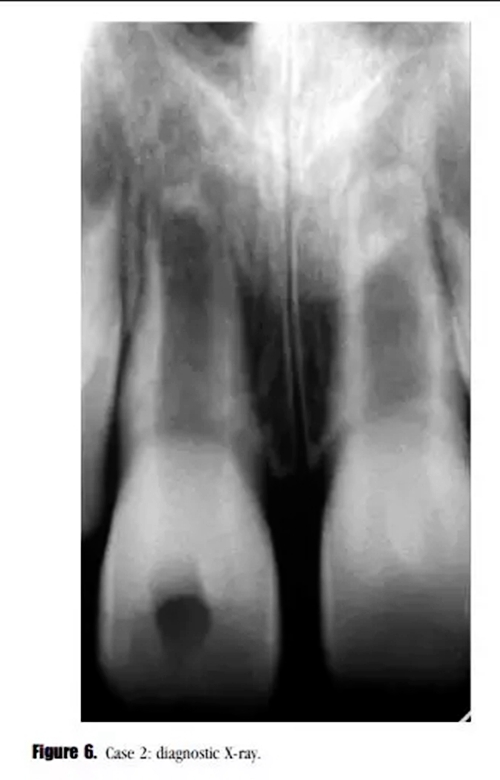

主訴:右上頜恒切牙區(qū)口腔前庭區(qū)腫脹。(圖6)。

??茩z查:牙齒輕微松動,可見開髓孔。叩診輕微不適,牙周探診深度在正常范圍內(nèi)。黏膜上可見一竇道。

輔助檢查:診斷X線示,牙根發(fā)育處于第4階段,未見明顯的根尖周透射影像,雙側(cè)中切牙根尖區(qū)可見阻射影像。21牙髓電活力測試結(jié)果正常。11診斷為:急性根尖周炎。